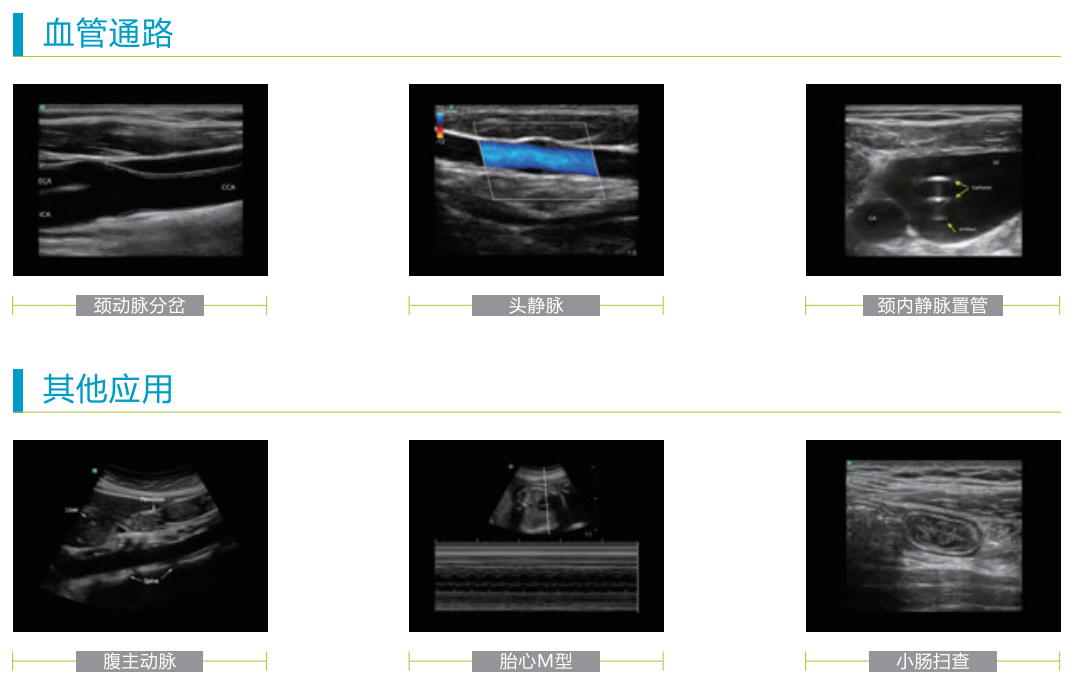

應用范圍

臨床醫(yī)生不可或缺的可視化工具

M-Turbo便攜式彩色超聲診斷系統(tǒng),可廣泛地應用于各臨床科室, 讓POC 可視化診療過程更便捷、更有效、更精確。

麻醉科、重癥科、急診科、超聲科、CVC、PICC、 泌尿科、肌肉骨骼、 心臟科、婦產(chǎn)科、外科、兒科、神經(jīng)科等各POC 臨床領域